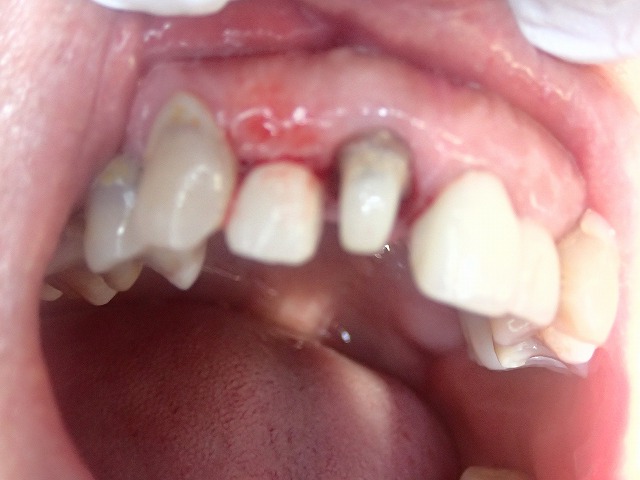

他院で制作したジルコボンドクラウンが

脱離したと来院されました。

20年以上も前の政策とのこと。

ややピンボケですがしっかりとした土台(コア)

が入っています。

透明度の高いジルコニアボンドクラウン。

透明度が高いので写真がピンボケ